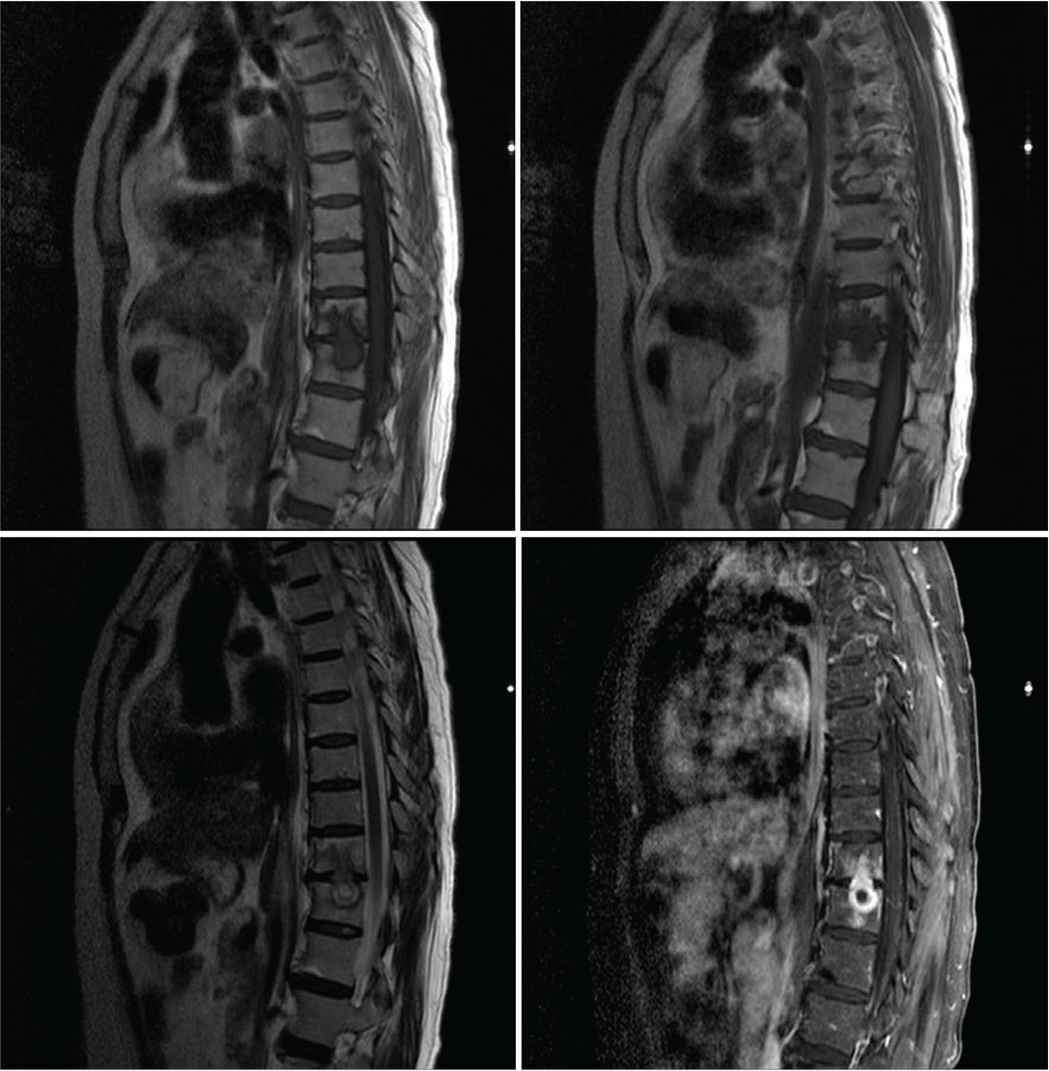

A 60-year-old female presented to the emergency department with headache, neck pain, and low back pain that started 6 months ago. Two weeks prior to presentation, she had difficulty walking with no sphincter control disturbance or sensory symptoms. She had no history of diabetes mellitus, infectious disease, or dyslipidemia. She is a housewife who is married and living with her children. Although no family history of tuberculosis was documented, she gave a strong history of contact with a patient who has open pulmonary tuberculosis that was not on treatment. Her systemic examination was normal including vital signs, lung auscultation, cardiac examination, and skin inspection. As part of her investigations, she had normal complete blood count, renal and liver function tests, and electrolytes including sodium, magnesium, and phosphate. Her erythrocyte sedimentation rate was high at 64. The result of her human immunodeficiency virus test was negative, and the chest X-ray was normal. Magnetic Resonance Imaging (MRI) of the whole spine revealed intramedullary dorsal (thoracic) ring-enhancing lesion at the level of T10–T11 (Figure 1). MRI of the brain showed diffuse meningeal enhancement with no intraparenchymal cerebral or cerebellar lesions (Figure 2). Cerebrospinal Fluid (CSF) analysis revealed a lymphocytic pleocytosis with a leukocyte count of 90 cells (reference range, 0–5), lymphocyte predominance (87%), raised protein of 236 mg/dL (reference range, 15–60 mg/100 mL), low CSF glucose 18 mg/dL (reference range, 50–80 mg/100 mL). CSF Gram stain, culture, and sensitivity were negative for all bacteria including mycobacterium tuberculosis. In addition, the Polymerase Chain Reaction (PCR) for viral, bacterial, and mycobacterial DNA was negative. Unfortunately, and despite tuberculous meningitis being the most likely diagnosis based on clinical and paraclinical data, the patient was not started on antituberculous medications. The treating infectious diseases consultant requested a brain and meningeal biopsy, which was declined by the patient’s family. The consultant refused to start the patient on antituberculous medications if no tissue is obtained for pathological confirmation of diagnosis. The patient’s condition deteriorated, and she was admitted to the intensive care unit with intubation and mechanical ventilation. The patient developed status epilepticus and was started on levetiracetam 1000 mg twice daily. She developed focal neurological deficits and multiple cranial nerve involvement. A repeated MRI of the brain showed an acute ischemic infarction with restricted left capsular, medial temporal, and hippocampal lesions in the apparent diffusion coefficient map (Figure 3). It also revealed persistence and even worsening of meningeal enhancement. Repeated CSF analysis revealed low glucose at 8, high protein at 255, and white blood cells count of 190 with lymphocytes (85%) and neutrophils (15%). Owing to the family request (based on neurology team recommendation) as well as clinical and radiological deterioration, the patient was started on antituberculous medications (rifampicin 600 mg, isoniazid 300 mg, pyrazinamide 1500 mg, and ethambutol 1200 mg) and oral corticosteroids through a nasogastric tube. This was several weeks after admission to the intensive care unit. Despite the advanced stage of the disease, the development of endarteritis obliterans with multiple ischemic strokes, and poor clinical condition, the patient’s condition improved, and her seizures stopped. Her neurological status improved, and she became more alert with better power in all limbs, and after 3 weeks, she was weaned off ventilation and was extubated. The patient was transferred to a rehabilitation center for an aggressive physiotherapy regimen, and the family was instructed to continue the antituberculous medications for a full 12-month period. Unfortunately, the patient died from neurological complications related to tuberculous meningitis (multiple infarcts with superadded massive pulmonary embolism).

Magnetic Resonance Imaging (MRI) scan of the whole spine showing intramedullary dorsal (thoracic) ring-enhancing lesion at the level of T10–T11.